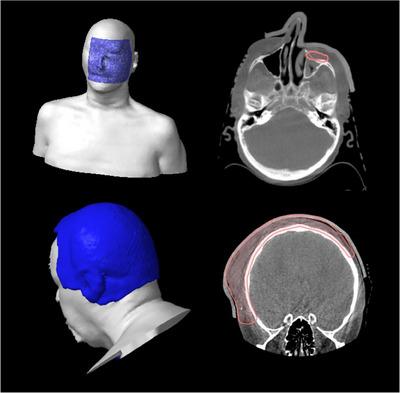

3D printed molds for bespoke bolus were created by exporting the DICOM structures of the bolus designed in the treatment planning system and manipulated to create a multipart mold for 3D printing. A silicone (Ecoflex 00-30) mixture is poured into the mold and cured to form the bolus. Molds for sheet bolus of five thicknesses were also created. A comprehensive FMEA was performed to guide workflow adjustments and QA steps.